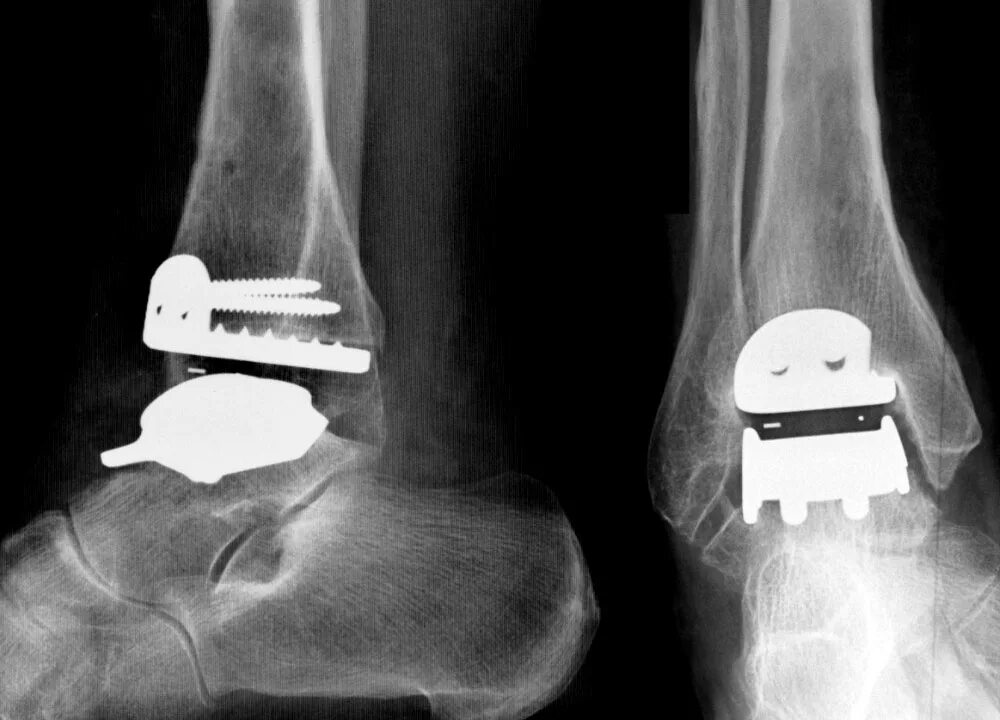

Артроз голеностопного сустава код